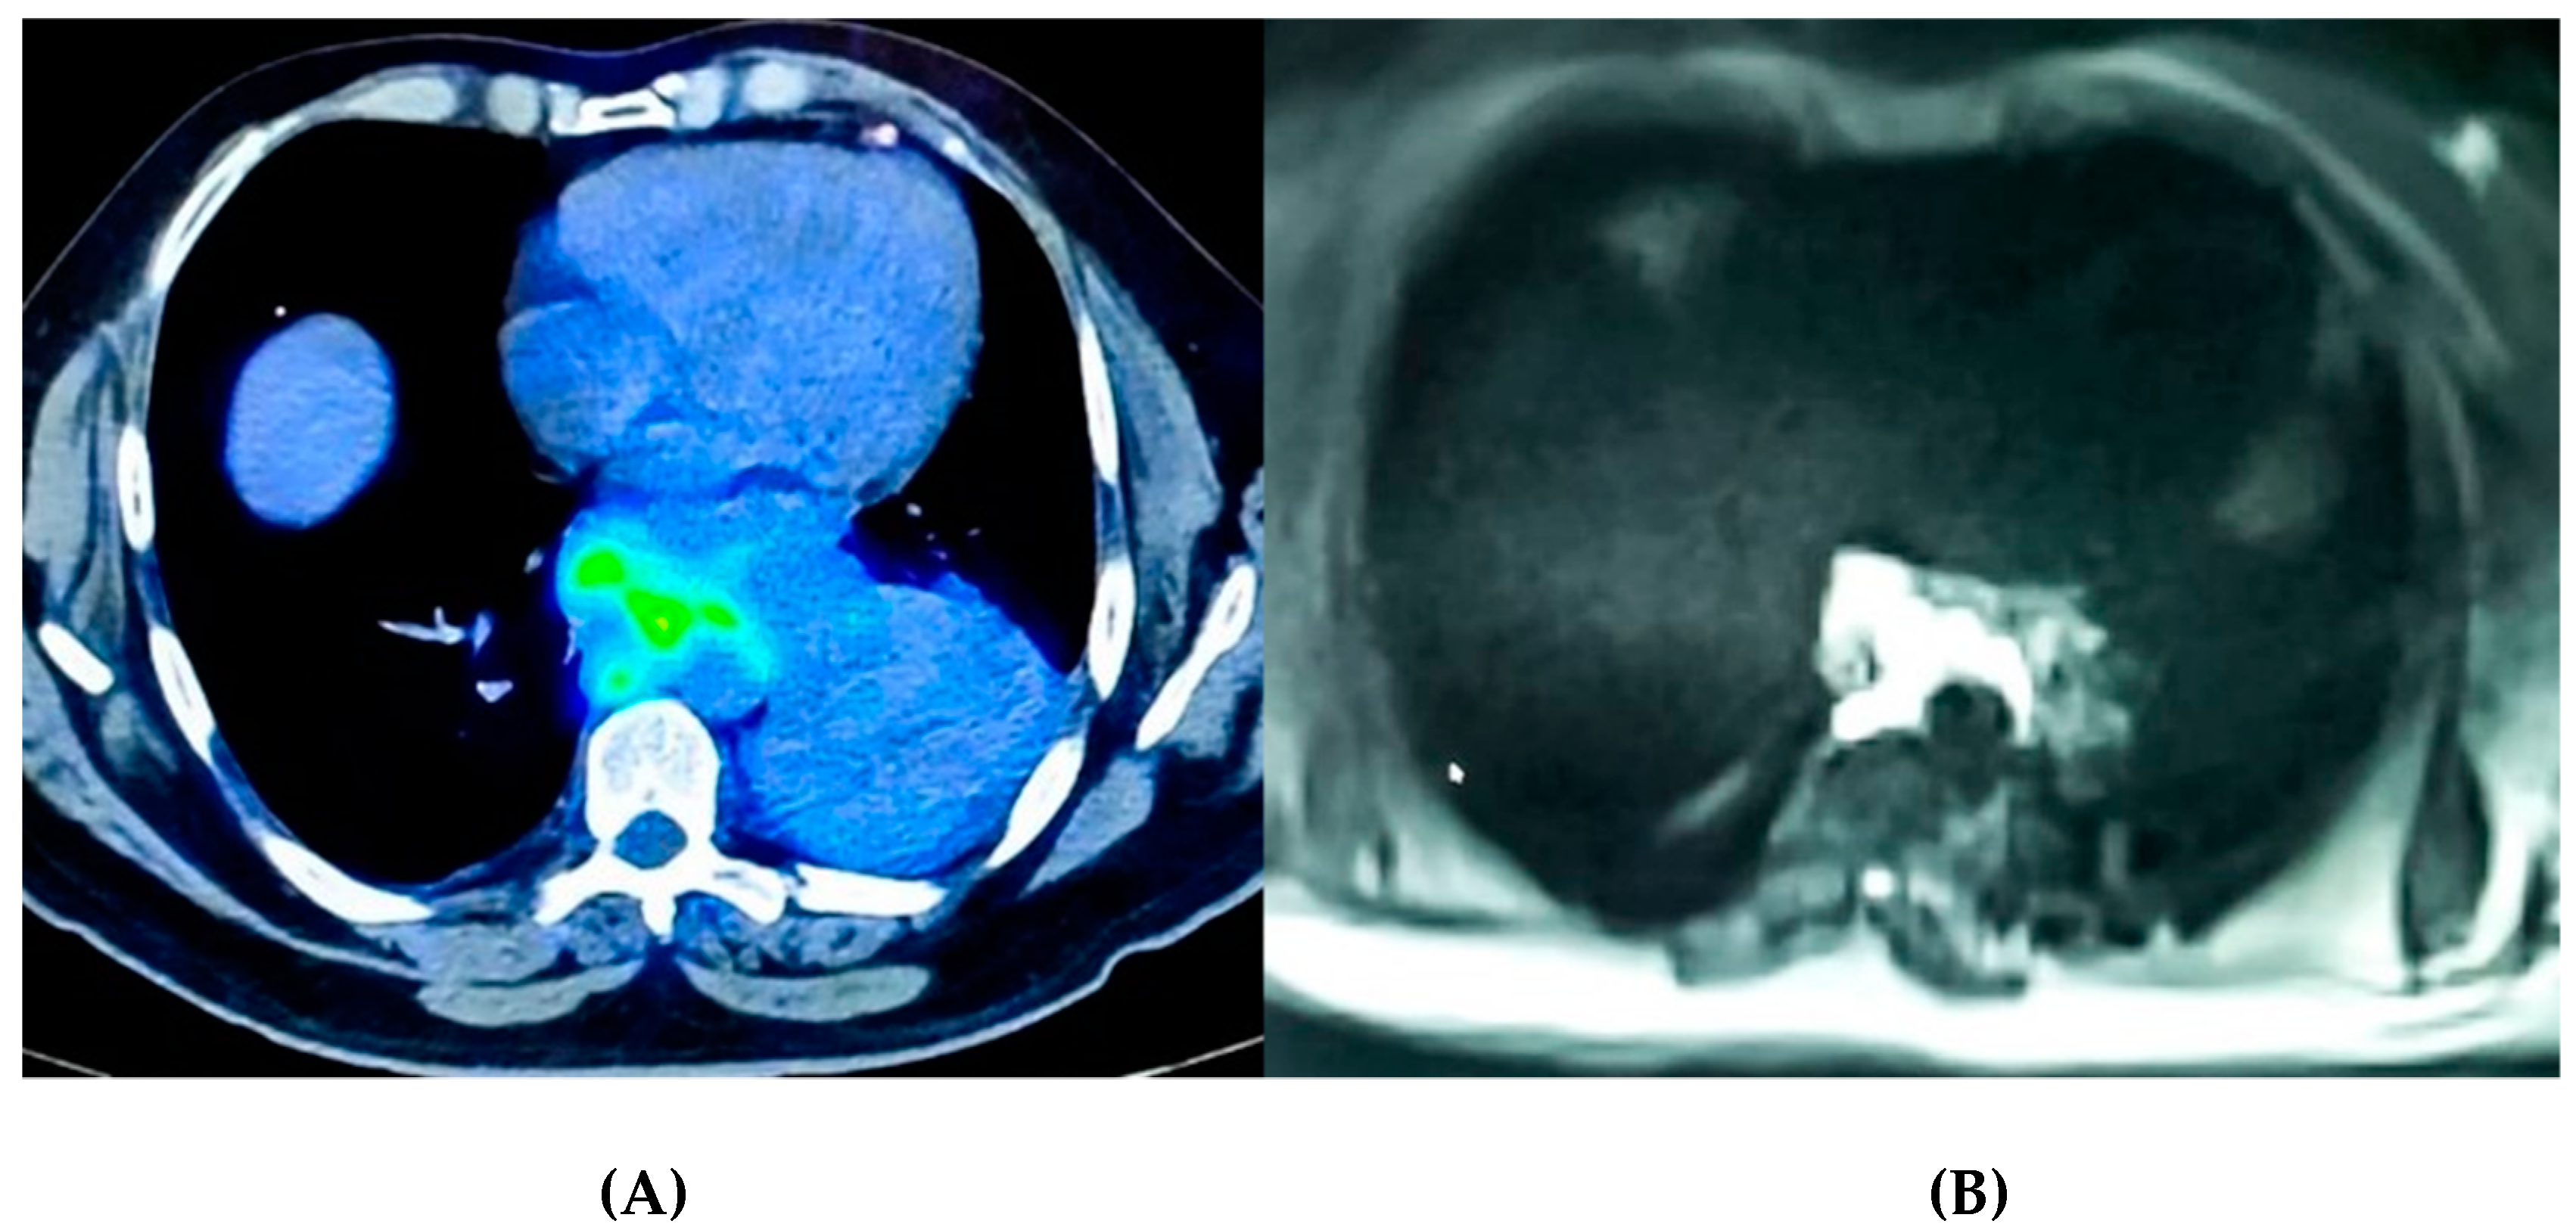

2.2. Imaging as a Tool to Assess Tumor Micro-Environment

- Gillies, R.J.; Kinahan, P.E.; Hricak, H. Radiomics: Images Are More Than Pictures, They Are Data. Radiology 2016, 278, 563–777. [Google Scholar] [CrossRef]

- Rizzo, S.; Botta, F.; Raimondi, S.; Origgi, D.; Fanciullo, C.; Morganti, A.G.; Bellomi, M. Radiomics: The Facts and the Challenges of Image Analysis. Eur. Radiol. Exp. 2018, 2, 36. [Google Scholar] [CrossRef]

- Sun, R.; Limkin, E.J.; Vakalopoulou, M.; Dercle, L.; Champiat, S.; Han, S.R.; Verlingue, L.; Brandao, D.; Lancia, A.; Ammari, S.; et al. A radiomics approach to assess tumour-infiltrating CD8 cells and response to anti-PD-1 or anti-PD-L1 immunotherapy: An imaging biomarker, retrospective multicohort study. Lancet Oncol. 2018, 19, 1180–1191. [Google Scholar] [CrossRef]

- Martini, K.; Frauenfelder, T. Old Borders and New Horizons in Multimodality Imaging of Malignant Pleural Mesothelioma. Thorac. Cardiovasc. Surg. 2021. [Google Scholar] [CrossRef]

- Armato, S.G.; Blyth, K.G.; Keating, J.J.; Katz, S.; Tsim, S.; Coolen, J.; Gudmundsson, E.; Opitz, I.; Nowak, A.K. Imaging in pleural mesothelioma: A review of the 13th International Conference of the International Mesothelioma Interest Group. Lung Cancer 2016, 101, 48–58. [Google Scholar] [CrossRef]